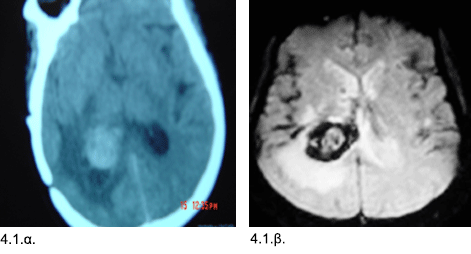

Εικόνες 4.1.α. και 4.1.β. Η αξονική τομογραφία αριστερά (4.1.α.) δείχνει την εκτεταμένη αιμορραγία σε βαθεία εντόπιση στη περιοχή συμβολής της κροταφοβρεγματικής χώρας, και η μαγνητική τομογραφία δεξιά (4.1.β.) δείχνει την υποκείμενη αιτία, δηλ. το σηραγγώδες αιμαγγείωμα που περιβάλλεται από ζώνη αιμορραγίας (σκουρόχρωμος δακτύλιος στην εικόνα.

Ιστορικό: Aσθενής 52 ετών με κεφαλαλγία, μείωση οράσεως και οίδημα οπτικών θηλών. Διαπιστώθηκε αιμορραγία που είχε προκληθεί από ρήξη σηραγγώδους αιμαγγειώματος. Έγινε κρανιοτομία και αφαίρεση του σηραγγώδους αιμαγγειώματος και αιματώματος. Η μετεγχειρητική πορεία ήταν ομαλή. Ο ασθενής δεν ανέπτυξε άλλα νευρολογικά προβλήματα, πέραν της μείωσης της όρασης, η οποία σταδιακά βελτιώθηκε.